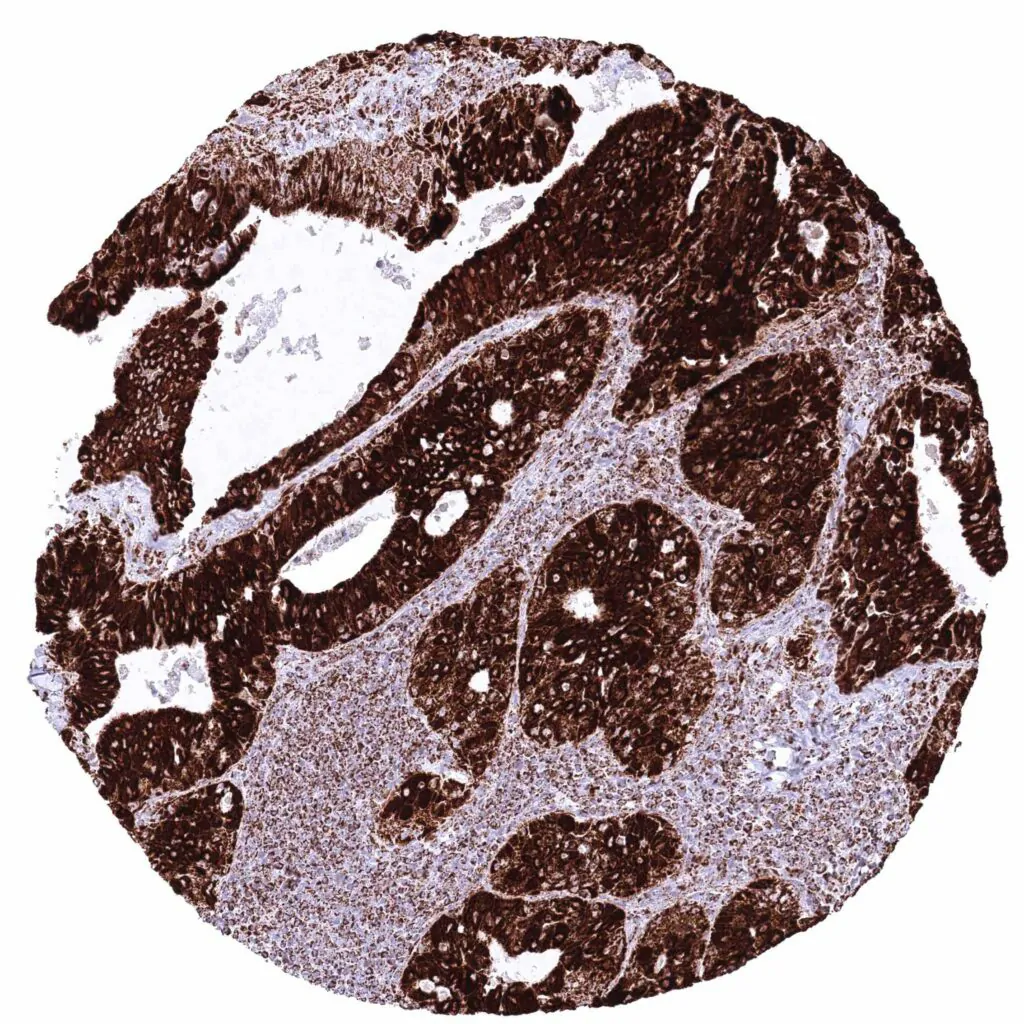

Kidney – Papillary renal cell carcinoma with moderate cytoplasmic ATP5J staining of tumor cells.